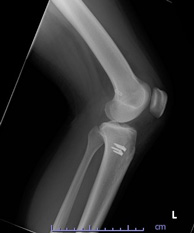

• 画像:術後レントゲン(側面)

術後レントゲン(側面)

• 画像:術後レントゲン(正面)

術後レントゲン(正面)